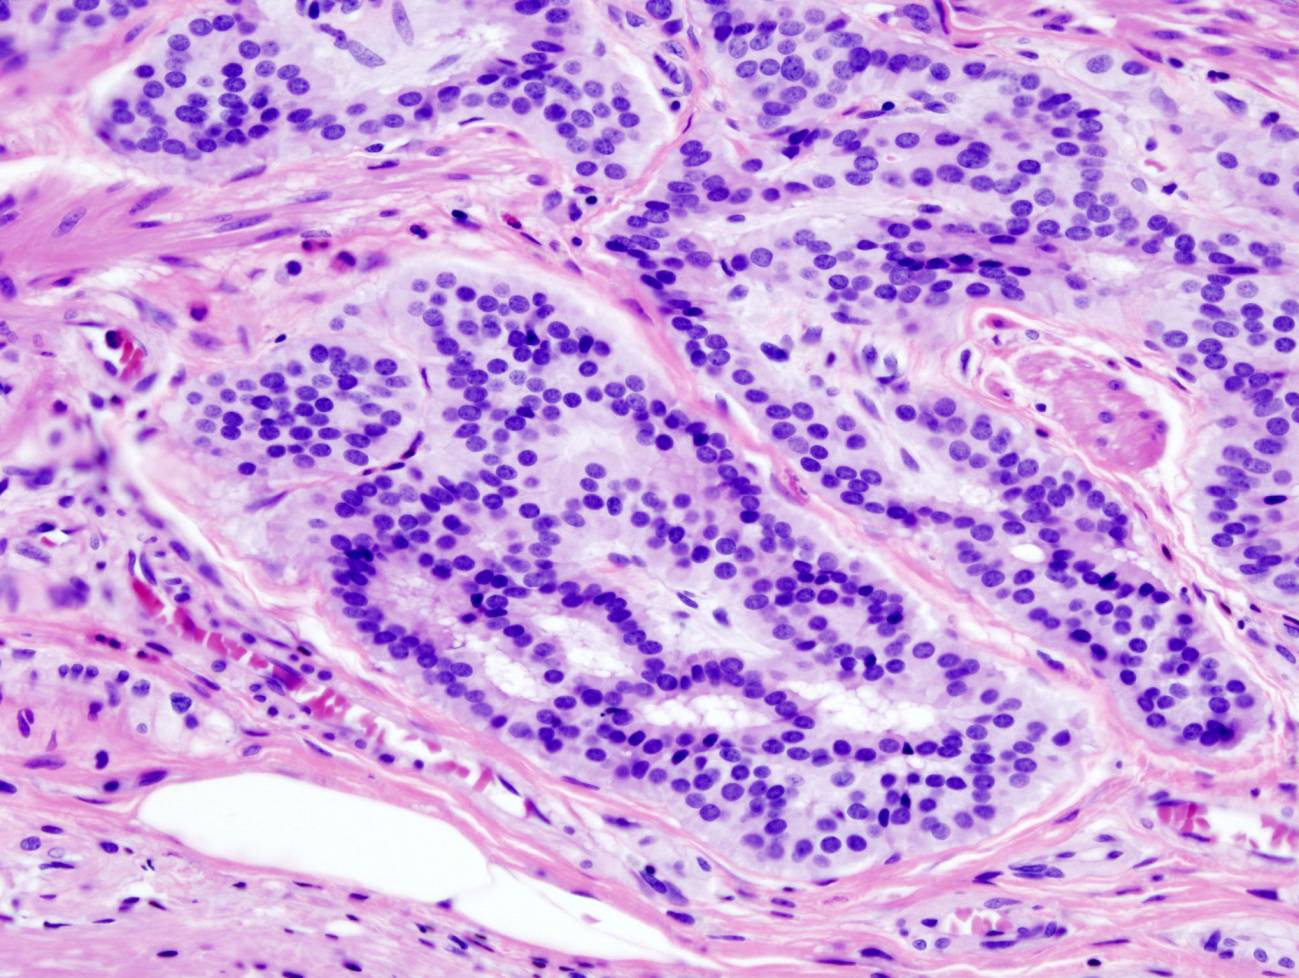

El consorcio HTAN (Human Tumor Atlas Network) publica simultáneamente 11 trabajos en distintas revistas del grupo Nature. En ellos se incluyen análisis sobre la arquitectura de los tumores y de su entorno en más de 2.000 pacientes y veinte localizaciones diferentes, lo que permitirá estudiar cómo se inician y evolucionan. Entre las novedades encontradas se encuentran nuevas pistas sobre el desarrollo de metástasis y resistencias a tratamientos y el hallazgo de que el cáncer colorrectal puede surgir de múltiples células con diferentes mutaciones que actúan colectivamente, en lugar de hacerlo desde un único clon inicial como se pensaba hasta ahora.

Estas publicaciones que se presentan explican y profundizan, por un lado, en el papel de células que están en el tumor, pero no son tumorales, lo que conocemos como ‘microentorno tumoral’. Estas incluyen a los vasos sanguíneos que dan nutrientes, oxígeno y factores, el sistema inmunitario que, en lugar de atacar al tumor, es engañado por este para explotarlo en su propio beneficio, células de soporte, etc.  Y se reeducan y evolucionan con el tumor.

Lo que es más interesante: estos trabajos confirman que en los tumores no todas las células deben acumular todas las mutaciones para iniciarse. El ‘cerebro’ del crimen puede estar repartido entre varias células tumorales, al menos en algunos tipos de cáncer de colon, pero será extensivo a muchos cánceres. En lugar de que una célula tumoral acumule todas las mutaciones y surja el tumor de una única célula tumoral que lo tiene que hacer todo, los tumores pueden surgir partiendo de varias células alteradas que se complementan y se van seleccionando conjuntamente.